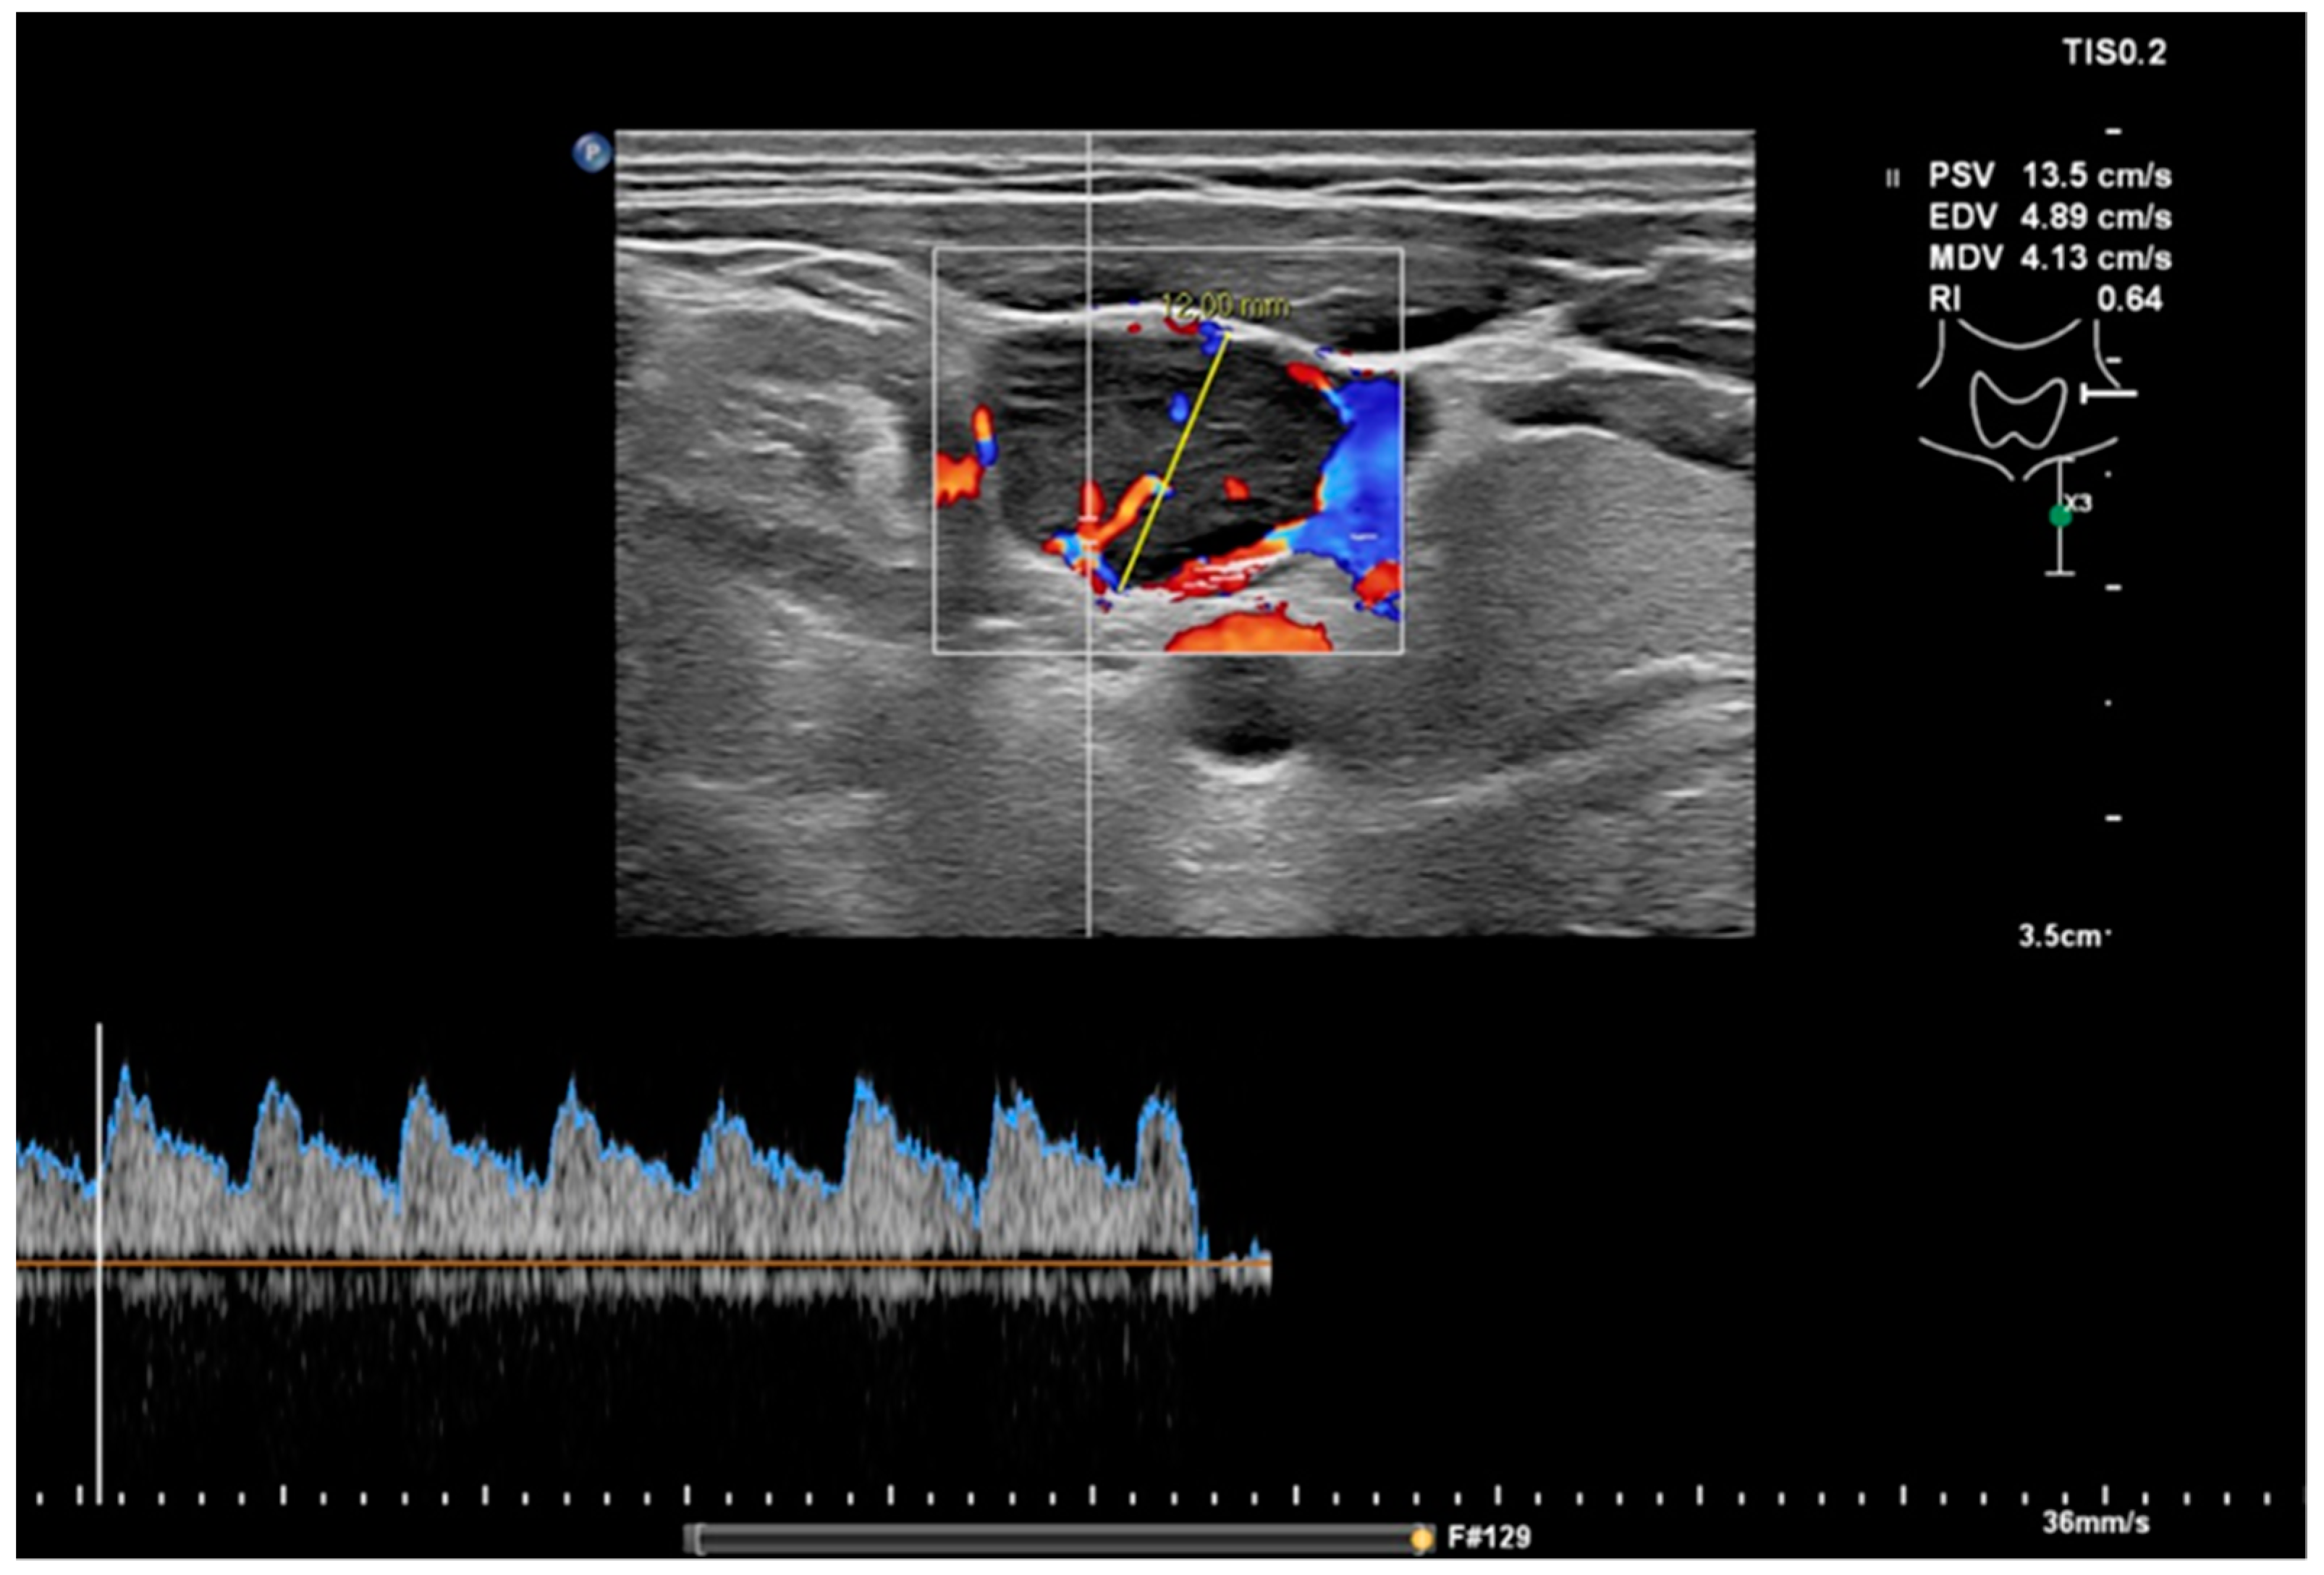

Figure 2.

Measurement of the RI in the same node as in Figure 1 with a value of 0.64, which would indicate a benign node.